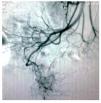

Mujer de 47 años, diabética e hipertensa de larga evolución, con antecedente de nefrectomía derecha por donación cinco años antes. Su padecimiento se inició a fines de 2008 con presencia de evacuaciones hematoquézicas y melena, por lo que requirió múltiples transfusiones. La endoscopia alta y colonoscopia no detectaron el sitio de hemorragia. En agosto de 2009 presentó choque hipovolémico secunadario a hematoquezia (hemoglobina de 3.5 g/dL) que requirió de transfusión de siete paquetes globulares. Se realizaron nuevamente endoscopia alta y colonoscopia que no detectaron en sitio de hemorragia. El gammagrama con eritrocitos marcados mostró concentración anormal del radioisótopo en la flexura hepática. Una enteroscopia no mostró sangrado evidente. Se practicó una angiografía selectiva de arteria mesentérica superior (AMS) en fase arterial (Figura 1), que mostró vasos de neoformación tortuosos e irregulares a nivel de íleon, sin retorno venoso temprano. La angio-tomografía computarizada (angioTC) con reconstrucción coronal y proyección de máxima intensidad (Figura 2), detectó una imagen hipodensa, con vasos tortuosos de neoformación que nacían de la AMS. La angioTC en 3D (Figura 3) reveló múltiples vasos de neoformación dependientes de la AMS localizados en íleon que demuestran una tumoración con gran vascularidad. Se realizó laparotomía exploradora encontrando un tumor a 90 cm de la válvula ileocecal (Figura 4). El análisis histopatológico determinó tumor estromal de alto grado con bordes quirúrgicos libres de lesión, con inmunohistoquímica para CD117 (Figura 5) y S100 positivos.

¿ Figura 2. AngioTC, con reconstrucción coronal y proyección de máxima intensidad. Se aprecia una imagen hipodensa, con vasos tortuosos de neoformación con origen en la AMS.